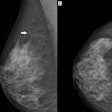

A new twist occurred this week in the long-running, heated debate over the true value of mammographic screening. France-based authors published a study yesterday that analyzed mortality data from Sweden to see if mammography screening reduced deaths from breast cancer, but the accuracy of their research was immediately questioned by the Hungarian-born screening pioneer, Dr. László Tabár.

For group editor Brian Casey's report, go to our Women's Imaging Digital Community, or click here. To read Tabár's counter opinion, click here.